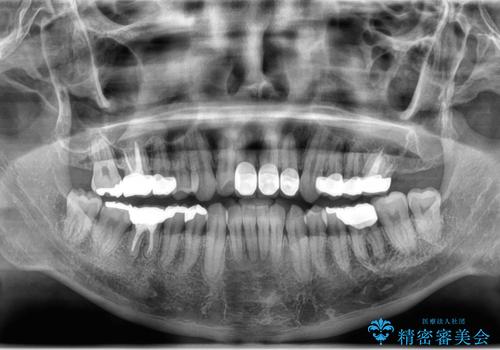

- 突き出た前歯の角度の改善と虫歯治療の改善を求めて来院されました。

虫歯を除去したのち、マウスピース矯正治療を行い、歯並びやがたつきを改善したのち、セラミックに置き換えることで審美性の向上を計画します。